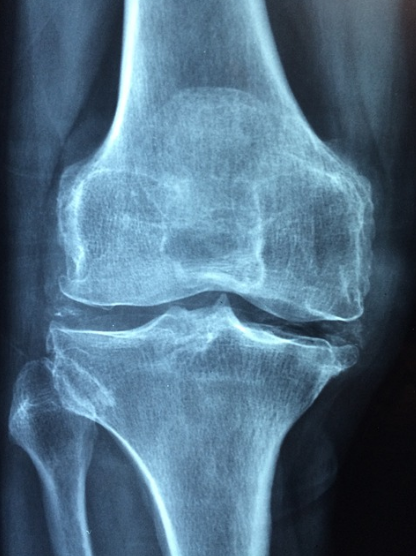

류마티스 관절염은 퇴행성 관절염과 증상이 유사해서 오진 가능성이 상당히 높습니다. 류마티스 관절염은 증상, 진찰, 혈액검사, 방사선 촬영을 통해 진단을 내립니다.

혈액검사로 류마티스 인자가 양성인지 확인하고 엑스레이 검사를 통해 관절의 손상여부를 확인하여 종합적 진단을 내리게 됩니다.